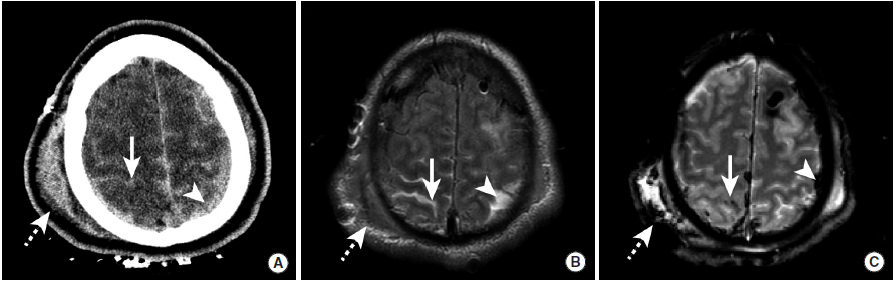

外伤性蛛网膜下腔出血

图1

本例为车祸导致的外伤性蛛网膜下腔出血。

图A:平扫CT显示脑沟内高密度影(长尾箭头),此外还可以看到左侧的硬膜下血肿(三角箭头)以及右顶骨处的帽状腱膜下血肿(虚线箭头)。

图B:MRI FLAIR序列同样可见脑沟内高信号,证实了蛛网膜下腔出血的存在,同时可见左侧硬膜下血肿和右侧帽状腱膜下血肿。

图C:GRE序列上,蛛网膜下腔出血和硬膜下血肿表现为低信号。